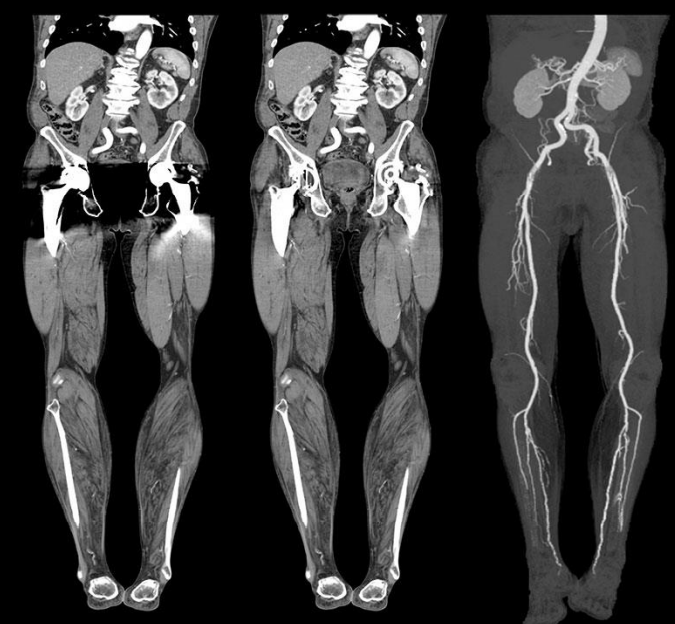

A angiotomografia é indicada quando existe a necessidade de examinar veias e artérias de determinadas regiões do corpo. Isso pode ocorrer devido à suspeita de aneurismas, estenoses, oclusões ou para acompanhamento preventivo de complicações vasculares após cirurgias.

A maior indicação para a angiotomografia de membro superior e inferior é a avaliação de obstruções arteriais (por tromboses ou estreitamentos), embora algumas tromboses venosas também possam ser diagnosticadas. Podem ser realizadas reconstruções multiplanares e em 3D.